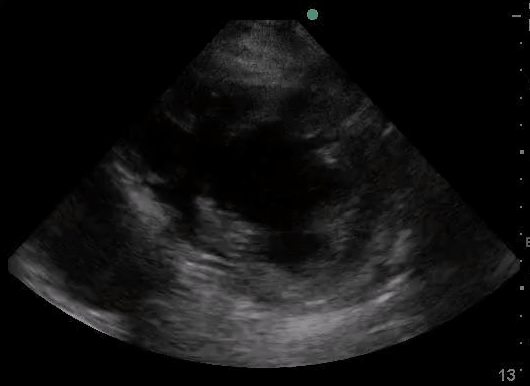

Case 2: Atrial Fibrillation, LVEF 30% with a small pericardial effusion